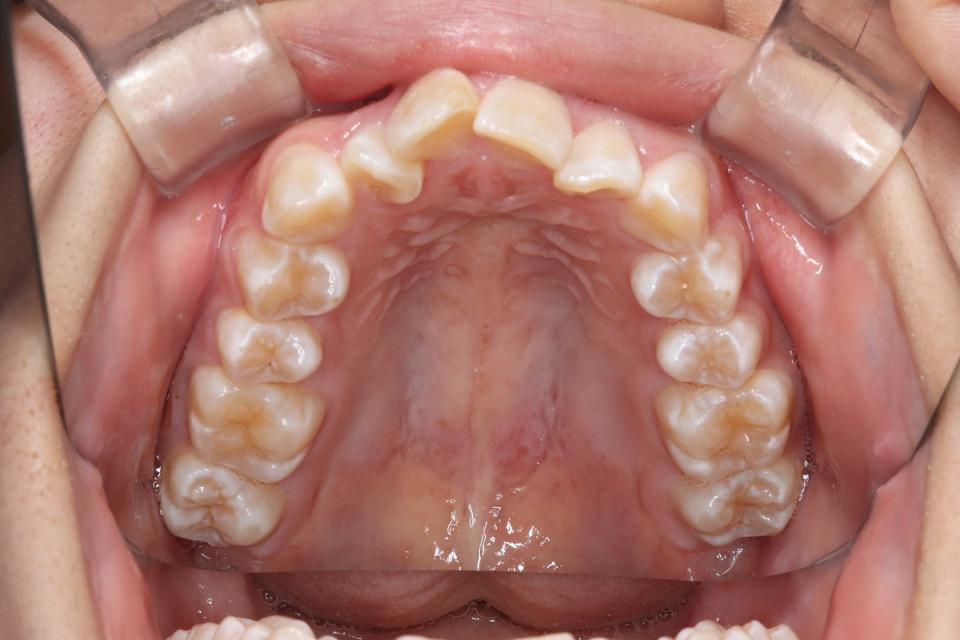

がたがた(叢生)のワイヤー矯正治療例(抜歯あり)

矯正治療前

20代女性の患者さんです。

上左右4番抜歯をして、上下の歯にワイヤー(マルチブラケット装置)をつけて治療しました。

きれいに並びきるために歯のやすりがけ(IPR)も行っています。